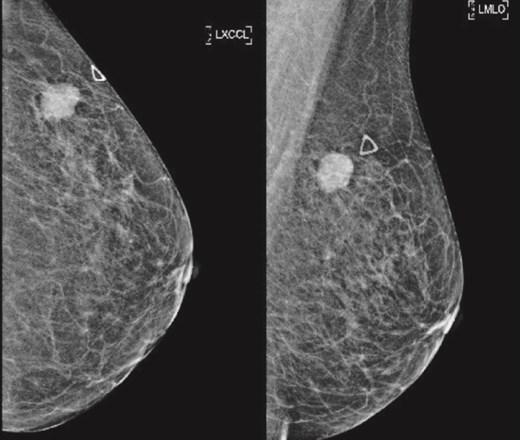

(Left) Mammography cranial-caudal view of left breast; (Right) Mammography mediolateral oblique view of the left breast: Left upper outer breast spiculated mass with minimal architectural distortion.

Patient C, aged 70, had no significant past medical history and initially presented to Otolaryngology with right-sided cervical lymphadenopathy. Excision biopsy confirmed a diagnosis of diffuse large B cell lymphoma (DLBCL). She then reported a 3-month history of a left breast lump. Clinical examination and imaging revealed a 20 mm lesion associated with ipsilateral axillary lymphadenopathy (Figs 7 and 8). Triple assessment confirmed triple negative invasive ductal carcinoma in the breast, whilst there were follicular cells in the nodes (Fig. 9). She underwent systemic chemotherapy for stage III diffuse large B-cell lymphoma using Rituximab, cyclophosphamide, doxorubicin, vincristine, and prednisolone (R-CHOP) protocol followed by weekly Paclitaxel for the concurrent breast cancer. She achieved clinical remission for lymphoma. Subsequently she underwent breast conserving surgery with sentinel node biopsy, and adjuvant chest radiotherapy.